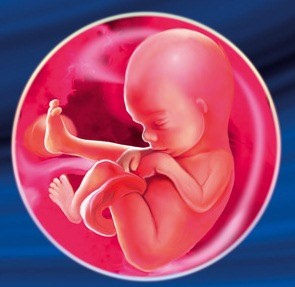

Розмір плода до 18 тижня становить в середньому трохи більше 14 см в довжину. Вага малюка - десь близько 200 р Незважаючи на збільшення його росту, він все ще вільно може пересуватися в порожнині матки, перевертатися, ворушити ручками і ніжками. Прийнято вважати, що такі рухи дуже корисні для його розвитку.

У дитинку до 18 тижня повністю сформувалися ручки і ніжки. На пальчиках сформувався унікальний рельєф шкіри, званий відбитком пальців. Активно розвивається головний мозок малюка, а разом з ним і імунна система, яка допомагає плоду потрапляє до нього інфекції.

Очки дитинку 18 тижнів ще закриті, проте він вже реагує на що проникає в животик мами світло. Варто відзначити, що відбувається також реакція малюка на шум.

Причому реагує малюк не на внутрішні звуки роботи організму мами - до них він звик, а на звуки, що доносяться ззовні. Гучні і різкі шуми лякають малюка, тому мамі не слід перебувати довго в місцях, де, наприклад, грає гучна музика. Якщо дитина все ж злякався гучного звуку і почав активно висловлювати це рухами, то мамі треба заспокоїти його за допомогою свого голосу. Можна тихо і ласкаво поговорити з ним, можна заспівати йому кілька колискових.